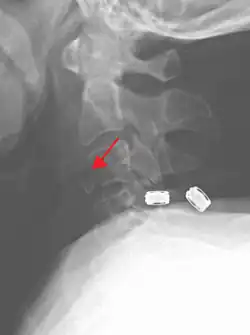

![]() | |

| A fracture of the base of the dens (a part of C2) as seen on CT | |